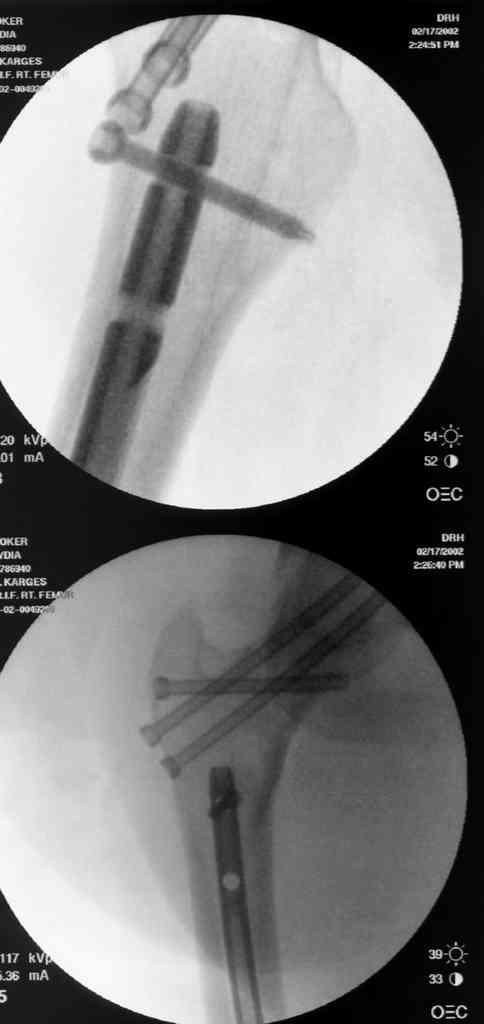

На снимках ложный сустав шейки бедра, несостоятельность фиксации. По положению шурупа можно предсказать ложный сустав, например, если screw backup за кортикальный слой около 15-20 мм, и также изменение угла от первоначального.

№2-3 типичная ошибка несоблюдения концепции параллельности шурупов, нарушение-фиксация поперечным допольнительным шурупом для приближения отломка в результате не сработало метод параллельных шурупов